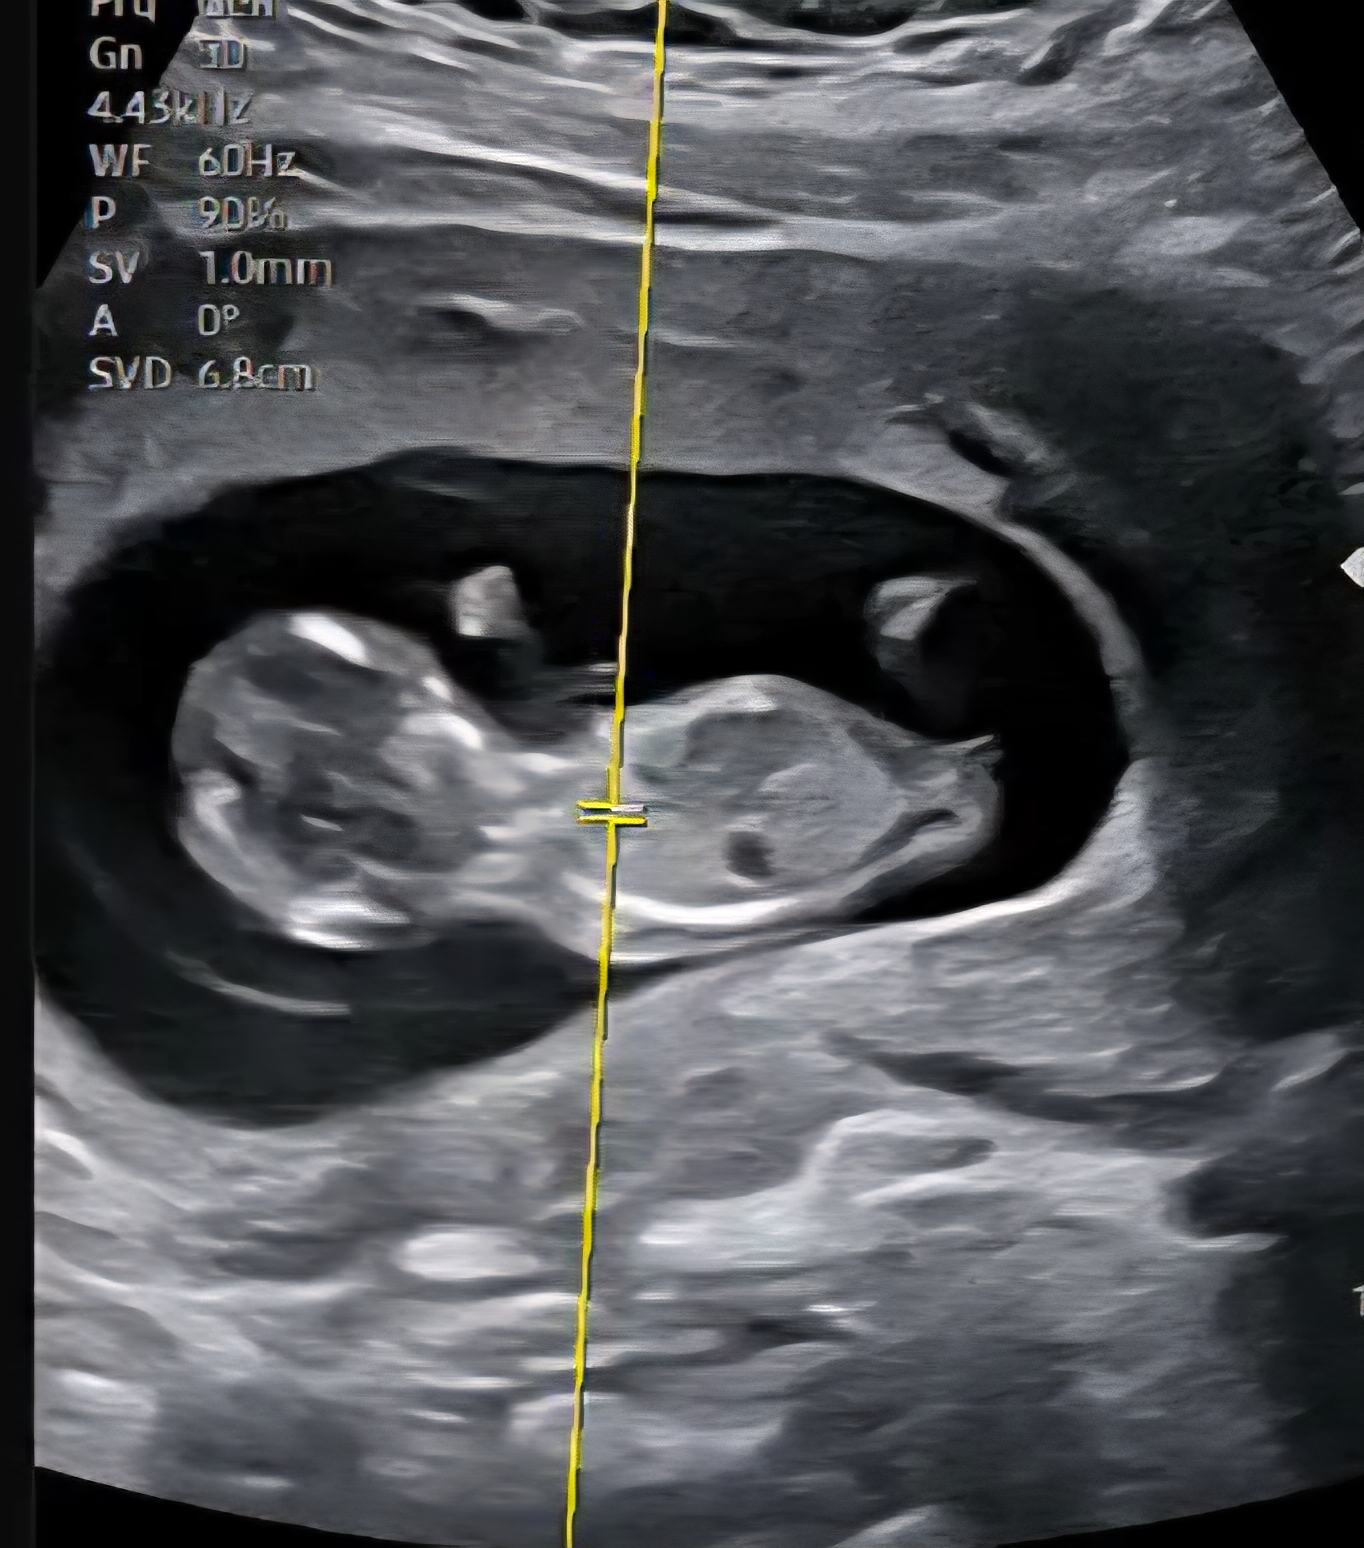

12주인데 각도법 봐주세용 사진업로드햇어오 ㅠㅠ

남편이 자꾸 ㄲㅊ가 보인다는데...ㅋㅋ 각도법으로 제가보면... 딸같아서 ㅋㅋㅋ 참견해주세용 ^^ 아까 사진업로드가 안된것같네요 ㅠㅠ